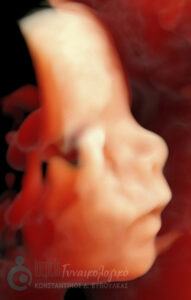

- Υπερηχογραφική εξέταση, η οποία συμβάλλει στη διαπίστωση της ενδομήτριας κύησης και αποκλεισμό της έκτοπης κύησης. Επιπλέον, μπορεί να διαπιστώσει εάν πρόκειται για μονήρη ή πολύδυμη κύηση, να ανιχνεύσει την εμβρυϊκή καρδιακή λειτουργία μετά τις 6 εβδομάδες και να προσδιορίσει υπερηχογραφικά την ηλικία κύησης, με βάση το κεφαλουραίο μήκος του εμβρύου μετά τις 8 εβδομάδες.